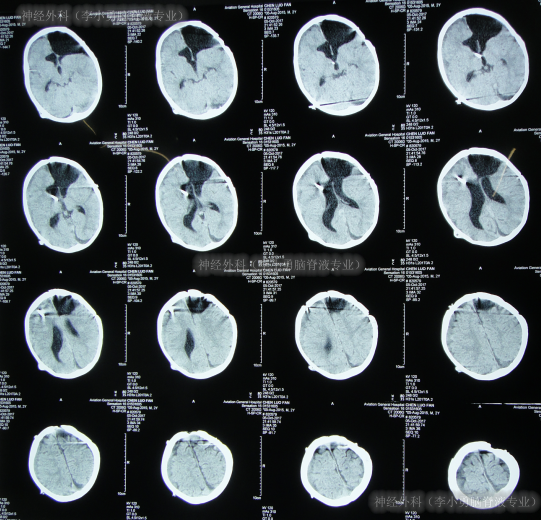

癫痫灶切除术后12天即2017年3月25日,复查头颅CT示癫痫病灶切除术后状态(图-4)。

图-4:2017年3月25日头颅CT

术后24天(2017年4月6日),复查头颅CT(图-5)示“癫痫切除术后现脑积水早期表现”,但未给予处理次日2017年4月7日“出院”。

图-5:2017年4月6日头颅CT